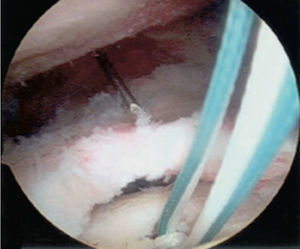

En la técnica de fila sencilla o una sola fila se colocan anclajes de 5,0 o 5,5 mm (titanio biodegradable o peek) en el margen lateral de la tuberosidad mayor, se pasan los puntos a través del tendón aproximadamente a 15 mm en sentido medial al borde de la rotura. Se utiliza el número de anclajes de acuerdo con el tamaño de la rotura. También se debe tener en cuenta con cuántas suturas está cargado el anclaje. En la mayoría de diseños tiene dos suturas reforzadas. Para las roturas en forma creciente se puede realizar la reparación con puntos sencillos, pero, cuando son lesiones de mayor extensión o en forma en L, se recomienda combinar puntos de borde a borde y fijación con anclajes (figs. 14–16).

En la técnica de doble fila se colocan uno o dos anclajes mediales en el borde articular de la cabeza humeral, se pasan puntos sencillos a través del tendón y se anudan las dos suturas de cada anclaje con nudos deslizantes bloqueados. Los anclajes laterales se colocan en el borde lateral de la tuberosidad mayor y se anudan con las suturas mediales, ya sea con nudos deslizantes bloqueados o con los sistemas de no nudos existentes en el mercado. Una de las principales complicaciones en la reparación del manguito de los rotadores es la rerrotura, pero es muy importante tener en cuenta que en muchas ocasiones no existe una correlación directa entre una rerrotura, ya sea parcial o completa, con los resultados clínicos y funcionales44. Sin embargo, existe una relación directa entre la cicatrización y la fuerza postoperatoria (figs. 17–19).